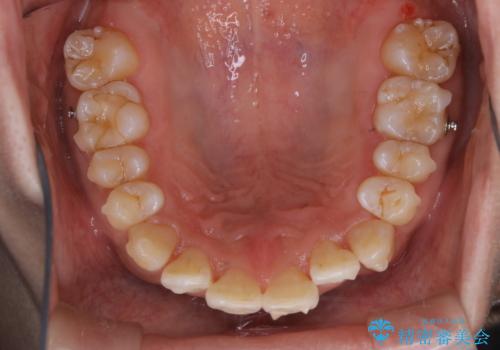

PMTCは30分コース・60分コースがあります。

30分コースでは主に前歯をメインに行います。

60分コースでは全体的に行います。

お口の状態、ご希望に合わせて当日担当の歯科衛生士とご相談してから行うことが可能です。

※着色や歯石の量、お口の状態により60分コースでも全ての汚れを除去することができない場合もあります。